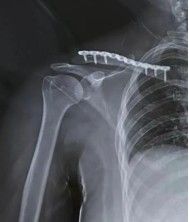

3.5 Систематические сжатые пластины, реконструкционные пластины или пластиковые LCP могут использоваться для закрепления переломов ключицы. Пластины плавно расположены над или передней к ключице. Пластины более сильнее в биомеханических травмах, когда они расположены превосходно, особенно если внизу есть разбитый перелом, и их проще в визуализации. Необходима бикортикальная фиксация винтов, и отверстия должны быть просверлены с большой осторожностью, так как внизу риск повреждения нервов и кровеносных сосудов. Преимущества: безопасное бурение переднего винтового канала, приложение пластины, легкая контур.

Выбор имплантатов пластин зависит от размера бокового костяного блока. Для бокового костяного блока требуется минимум 3 бикортикальных винта. В идеале, винты натяжения должны использоваться для наклонных переломов. Если костный блок слишком мал для фиксации, может использоваться крючка ключица.